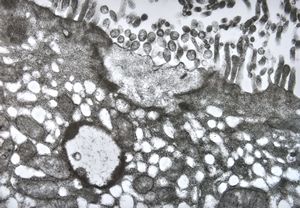

M,33y. | microsporidiosis (or cryptosporidiosis) - duodenum-posttransplantation immunodeficiency (HE and semithin section)

M,33y. | microsporidiosis (or cryptosporidiosis) - duodenum-posttransplantation immunodeficiency